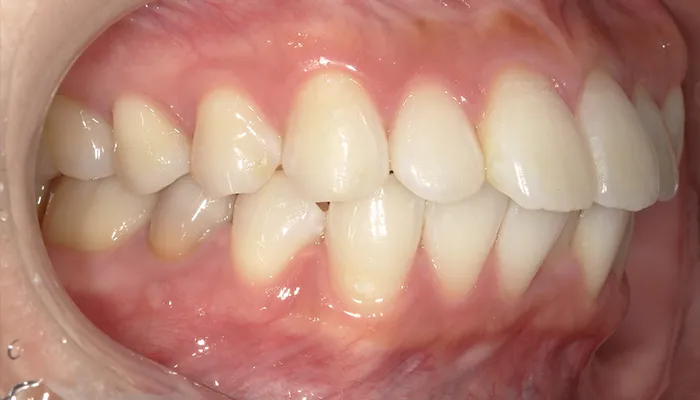

治療後の口腔内写真

術後の口腔内写真

右下5番のインプラントは良好に骨結合し、自然な形態と色調の補綴物を装着しました。

インビザライン矯正により歯列が整い、清掃性・咬合バランスともに改善しました。

ホワイトニングにより歯全体の色調が明るくなり、笑顔の印象が大きく改善しました。

患者様は審美性・機能性ともに大変満足していらっしゃいました。